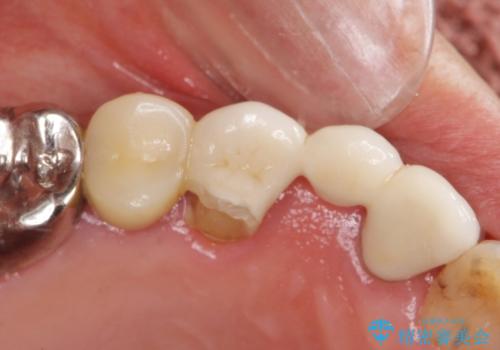

口腔内を精査したところ、右上のブリッジの内側(口蓋側)がかけており、下の前歯(右下1)には唇舌側に瘻孔を伴う大きな根尖病変ができていました。

右上のブリッジ(右上④3②)のやりかえと、下の前歯(右下1)の根管治療を行った後セラミッククラウンによる補綴治療を行いました。

右上④3②ブリッジ:オールセラミッククラウン スタンダード